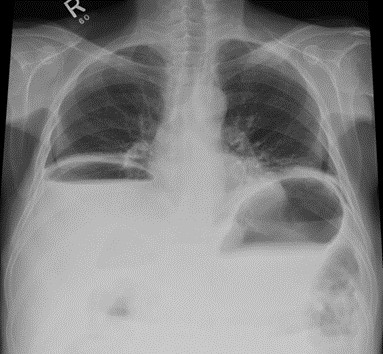

Poniższy radiogram jest charakterystyczny dla: